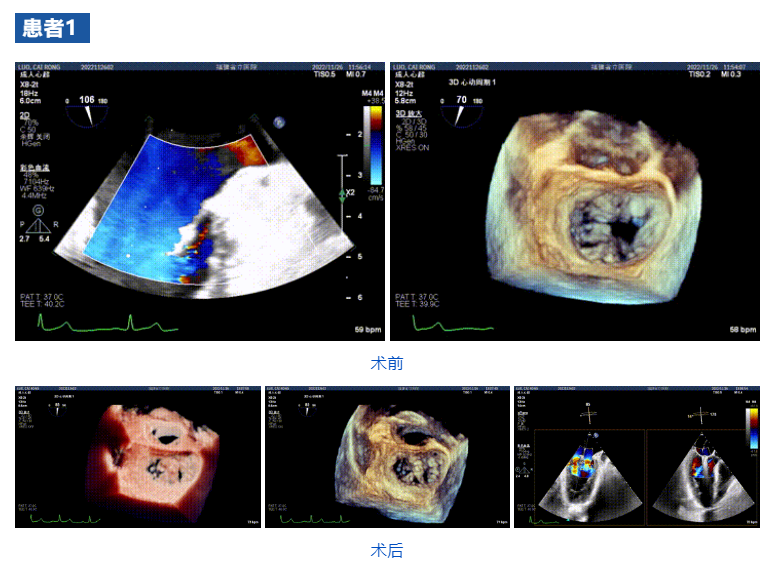

接受治療的三例患者均為器質(zhì)性重度二尖瓣反流(DMR)患者,術(shù)前超聲提示二尖瓣后葉脫垂伴4+反流,左室舒張功能減退。郭延松教授攜同團(tuán)隊(duì)成員陳新敬副教授和洪景宣、方明程、楊清勇主治醫(yī)師、心外科丁杭主任以及超聲科賴寶春、葉振盛主治醫(yī)師共同進(jìn)行病情討論??紤]到患者高齡、基礎(chǔ)疾病多、STS評(píng)分高,為外科手術(shù)極高危患者,不適合進(jìn)行外科開胸二尖瓣手術(shù),因此決定為患者實(shí)施經(jīng)導(dǎo)管緣對(duì)緣修復(fù)介入術(shù)(JensClip經(jīng)導(dǎo)管瓣膜夾系統(tǒng))。

在浙江大學(xué)醫(yī)學(xué)院附屬第二醫(yī)院王建安教授團(tuán)隊(duì)的支持下,手術(shù)經(jīng)股靜脈-房間隔入路,采用全身麻醉插管,在TEE和DSA引導(dǎo)下完成房間隔穿刺。置入JensClip瓣膜夾系統(tǒng)后,在左房調(diào)整瓣膜夾的位置和軸向,后進(jìn)入左室,在TEE引導(dǎo)下捕捉二尖瓣前后瓣葉,并關(guān)閉瓣膜夾。經(jīng)TEE反復(fù)確認(rèn)手術(shù)效果后最終鎖定并釋放瓣膜夾。術(shù)后即刻超聲顯示瓣膜夾位置穩(wěn)定,功能良好,二尖瓣反流由術(shù)前4+減少至微量,手術(shù)圓滿成功。